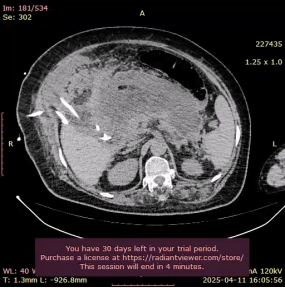

2025年3月14日我科急症收治一名64岁女性患者,BMI:32.5诊断:急性重症胰腺炎(胆源性)全身炎症反应综合征(SIRS),入院腹痛剧烈,伴腹胀发热,既往有高血压病史。辅助检查:实验室检查:血淀粉酶871 U/L,甘油三酯5.6 mmol/L,CRP 180 mg/L,乳酸3.8 mmol/L,肌酐:555.05umol/L。急性重症胰腺炎(SAP)是一种起病急、进展快、并发症多的高危疾病,死亡率可达20%-30%(根据2021年国际胰腺病协会数据)。若不及时治疗,可能引发多器官衰竭。

治疗第四周,患者再次高热,CT证实胰腺坏死灶感染并发脓毒血症。本病例遵循“Step-up approach”模式,优先微创干预,避免早期开放手术的高风险。行胰腺穿刺引流术。每日引流约600ml。治疗后患者病情逐步平稳,成功助力患者度过第二个死亡高峰期。